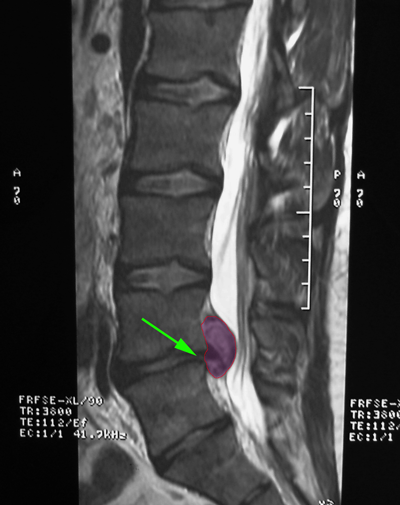

Κήλη οσφυϊκού μεσοσπονδυλίου δίσκου, επίπεδο |